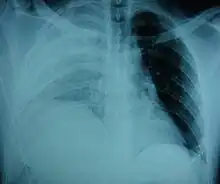

Physical examinations are not accurate, as there is usually no specific physical sign that can be used to diagnose this condition.[3] Thoracoscopic and laparoscopic methods can be accurate.[12] Chest X-ray is known to be unreliable in diagnosing diaphragmatic rupture;[4] it has low sensitivity and specificity for the injury.[5] Often another injury such as pulmonary contusion masks the injury on the X-ray film.[6] Half the time, initial X-rays are normal; in most of those that are not, hemothorax or pneumothorax is present.[4] A nasogastric tube from the stomach may appear on the film in the chest cavity; this sign is pathognomonic for diaphragmatic rupture, but it is rare.[4] The X-ray is better able to detect the injury when taken from the back with the person upright, but this is not usually possible because the person is usually not stable enough; thus it is usually taken from the front with the person lying supine.[5] Positive pressure ventilation helps keep the abdominal organs from herniating into the chest cavity, but this also can prevent the injury from being discovered on an X-ray.[4]